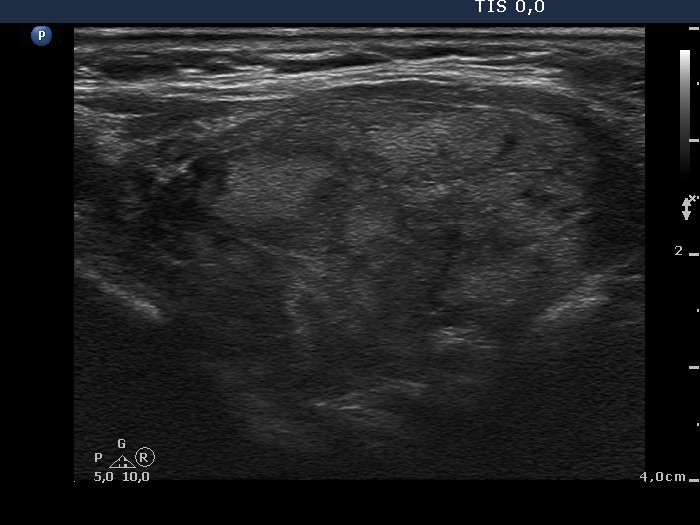

Case 739

Follow-up investigation two years later (ultrasonographic picture 7)

Left lobe, another longitudinal scan.